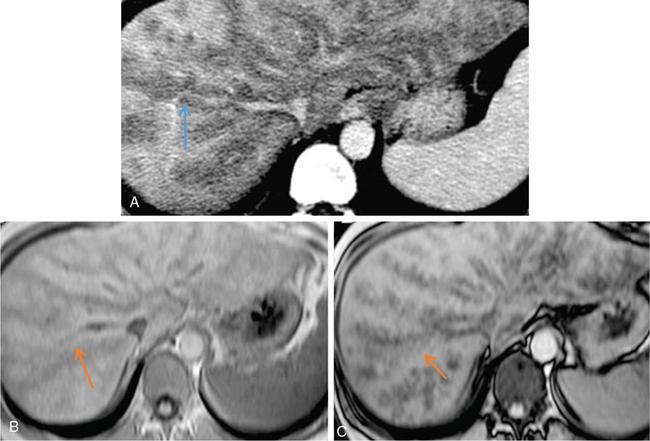

Excessive triglyceride accumulation within hepatocytes is defined as hepatic steatosis. Major conditions associated with hepatic steatosis include alcoholic fatty liver disease (AFLD) and nonalcoholic fatty liver disease (NAFLD). Causes of hepatic steatosis are discussed in Table 9.10.3. NAFLD is the most common form of hepatic steatosis and discussed in detail below. Up to 90% of patients with chronic alcoholic intake have fatty liver. Those with pure AFLD have a 10% risk of progressing to cirrhosis. Consumption of 30 g ethanol/day shows increased risk of chronic liver disease and cirrhosis. Other risk factors include female sex, obesity, cigarette smoking, obesity and associated risk factors. These factors are divided into 2 main categories which can cause fatty liver: inborn errors of metabolism and acquired metabolic disorders. Inborn errors of metabolism include abetalipoproteinemia, galactosemia, glycogen storage disease, hereditary fructose intolerance, homocystinuria and Wilson disease. Inflammatory bowel disease, jejunoileal bypass, malnutrition, starvation and total parenteral nutrition are acquired metabolic factors associated with increased risk. Chronic HCV infection, is associated with hepatic steatosis, with prevalence of 40%–80%. Hepatic steatosis can be seen as an adverse reaction to some medications such as tetracycline, valproic acid, some of chemotherapeutic agents, dexamethasone, amiodarone, methotrexate, tamoxifen and acetylsalicylic acid. Either microvesicular or macrovesicular steatosis can be observed in drug-induced hepatic steatosis. It generally occurs with therapy lasting several weeks or months and is reversible after discontinuation. The leading cause of hepatic steatosis in paediatric population is NAFLD. Six per cent of these patients develop cirrhosis and end-stage disease. Other less common causes include starvation and malnutrition, drugs (glucocorticoids, oestrogens, tetracyclines, and methotrexate), intoxications (carbon tetrachloride, organic phosphates, organic solvents, and alcohol), metabolic disorders, hepatitis C infection, and total parenteral nutrition. NAFLD is defined as steatosis affecting >5% of hepatocytes in the absence of a secondary cause. NAFLD represents a spectrum of disease, ranging from simple steatosis to steatohepatitis through to fibrosis and cirrhosis and in some cases hepatocellular carcinoma. NAFLD is a growing epidemic worldwide in part due to obesity and insulin resistance leading to liver accumulation of triglycerides and free fatty acids. Nonalcoholic steatohepatitis (NASH) is defined by histologic terms as a necroinflammatory process whereby the liver cells become injured in a background of steatosis. 20% of patients with NAFL progress to NASH, which progresses to fibrosis and cirrhosis over a 15-year time period (Fig. 9.10.3). The definition of NAFLD requires imaging or histology evidence of steatosis and no causes for secondary hepatic fat accumulation like significant alcohol intake, drugs or hereditary disorders (Table 9.10.4). The incidence of NAFLD ranges from 20% to 30% in Western countries and 5%–18% in Asia. As it currently stands, NAFLD represents the second most common reason to be listed for a liver transplant. The prevalence of NAFLD is higher in patients with obesity, diabetes, and patients with hyperlipidaemia. Prevalence increase with age from less than 20% at age 20 to more than 40% over 60 years of age. Males show a higher risk for progression to NASH and fibrosis (Table 9.10.5). Up to 90% of patients with NAFLD have simple steatosis, and about 30% of patients with NAFL develop NASH, and in again about 30%–40% of NASH patients the disease progresses to manifest fibrosis and cirrhosis NAFLD related cirrhosis has a 10-year mortality of 25% and a 5% chance of developing end-stage liver disease and HCC. The theory implicated in the pathogenesis of NAFLD is the two-hit theory. Insulin resistance, enhanced dietary influx and increased hepatic lipogenesis leading to accumulation of triglycerides (TG) and FFA in the hepatocytes is the first hit. The lipid peroxidation, mitochondrial dysfunction and inflammation resulting in hepatocyte damage and development of liver fibrosis is the second hit. The stages of NAFLD on histology range from steatosis initially to hepatic fibrosis in late stages. In the steatotic stage large (macro-) and small (micro-) vesicles of fat, predominately triglycerides, accumulate within hepatocytes. The affected parenchyma is divided into thirds: 5%–33%, 34%–66% and >66% and graded as mild, moderate and respectively. Ballooned hepatocytes with accompanied steatosis and inflammation are characteristic of the steatohepatitis stage. Fibrosis has a characteristic appearance with early lesions showing a perisinusoidal deposition followed by periportal fibrosis which progresses to bridging. Raised GGT is the most common liver enzyme elevated in NAFLD. Transaminases are within normal range in 80% patients. No specific blood tests can diagnose NAFLD. Liver biopsy has remained the gold standard for diagnosis and quantification of liver fat. Drawbacks, however, include invasive nature, sampling error and procedure related complications like bleeding. Various imaging techniques are currently available in diagnosing and quantifying liver fat. MRI in particular proton density imaging and MR Spectroscopy have revolutionized imaging of fatty liver. Normal liver parenchyma is the same as or slightly more echogenic than the adjacent kidney and spleen. Fat deposition leads to increased echogenicity of liver. Decreased beam attenuation in patients with fatty change leads to poor visualization of structures such as intrahepatic vessels, bile ducts and liver lesions and in severe cases diaphragm (Table 9.10.6). Fatty liver can be graded on USG as: US has a fair accuracy of detecting the moderate to severe hepatic steatosis with sensitivity of about 90% and specificity of about 95% for patients without concomitant chronic liver disease. Ultrasound is observer and equipment dependent. Confounding factors such as large body hiatus may lead to overestimation of hepatic steatosis due to beam attenuation by overlying fat. Conditions like fibrosis, inflammation can affect interpretation. The ratio between the mean brightness level of liver and right kidney is called the Hepatorenal sonographic index. A cut off of 1.49 has a high sensitivity and specificity for diagnosis of steatosis >5%. The main advantages of CT for assessing steatosis are relatively fast acquisition, ease of performance, and quantitative results. Estimation of fatty liver is done on non-contrast enhanced images. The normal liver density is around 60 HU, which is approximately 10 HU higher than normal spleen. Fat accumulation in the liver manifests as proportionate decrease in density. Both the absolute and relative (to the spleen) values are used to characterize steatosis; a cut-off value of 40 HU has been suggested to predict fat content greater than 30% (Figs. 9.10.6 and 9.10.7) Attenuation difference between liver and spleen on unenhanced CT scan is a commonly used quantitative parameter to evaluate hepatic steatosis. This avoids errors in attenuation value measurement from different CT scanners and different reconstruction algorithms. Normal liver parenchymal attenuation on nonenhanced CT is slightly higher than the spleen. Liver attenuation progressively decreases as percentage steatosis increases (Table 9.10.7) (Fig. 9.10.8) Methods of liver fat quantification on CT have been discussed in details in chapter on liver transplant. Limited diagnostic accuracy for detecting mild degree hepatic steatosis is one of major drawback of CT. Disorders causing hyperdensity of liver such as iron, glycogen deposition can lead to errors in interpretation. The concomitant presence of iron and fat may not be accurately diagnosed on CT. Low CT density values may also be caused by oedema and inflammation. Likewise, the spleen is an imperfect reference standard as it can be affected by haemosiderosis and haemochromatosis in a small minority of patients. Dual-energy CT with its ability to perform material decomposition is more accurate in quantifying hepatic steatosis and allows staging of fibrosis. Imaging is done with two different energies (typically 80 kVp and 140 kVp). DECT has the potential to quantitate liver fat content independent of ROI (region of interest) placement. Magnetic resonance imaging (MRI) is presently the most accurate imaging modality for the evaluation of hepatic steatosis. Several different methods have been developed and introduced in MRI for the evaluation of hepatic steatosis. In this technique typically, two gradient echoes are acquired, one employing a TE in which the water peak (4.7 ppm) and the dominant fat peak (1.3 ppm) are ‘out of phase’ and hence subtractive (SOP), and the other using a TE in which the two peaks are ‘in phase’ and therefore additive (SIP). Because two echoes are acquired, this is often called ‘dual-phase’ or ‘dual echo’ imaging. Fat Signal Percentage is calculated as [SIP – SOP]/[2 × SIP] ×100. The dynamic range of magnitude based chemical shift techniques has typically a 0%–50% signal fat-fraction (Fig. 9.10.9) This technique uses both magnitude and phase information from three or more images acquired at different echo times appropriate for more accurate separation of water and fat signals as against only magnitude information in dual-echo. These methods provide estimates of fat fraction with a dynamic range of 0%–100%. Proton density Fat fraction (PDFF) is calculated as Sf/(Sw + Sf) where Sw = SI of the water component, Sf = SI of the fat component. PDFF specifically reflects the concentration of triglycerides in the hepatocytes as lipids within the other structures such as cell membranes and organelles are occult. Sensitivity up to 96% and specificity up to 100% for detecting any degree of steatosis have been reported. A fat-fraction threshold of 5.56% is commonly used to define steatosis; however, the optimal cut-off value still needs to be defined (Figs. 9.10.10 and 9.10.11). MRS can directly measure the chemical composition within tissue based on the frequency composition of the signal originated from the voxel of interest. Water proton peak appears as a single peak at 4.7 ppm, whereas fat peaks appear as multiple peaks around 1.3 ppm. PDFF can be calculated as the ratio of the sum of the signal intensities derived from the protons in fat divided by the sum of the signal intensities originated from the protons in both fat and water (Fig. 9.10.12). TABLE 9.10.8 MRS data are usually obtained from a single voxel manually placed in the liver parenchyma usually right posterior segment of the liver. Reported MRS sensitivities and specificities for detection of mild hepatic steatosis are 80.0%–91.0% and 80.2%–87.0%, respectively, outperforming CT and US. MRS can also provide excellent reproducibility of measurement. It is also unaffected by confounding factors like fibrosis, iron overload and glycogen. Small sample volume usually less than 3 × 3 × 3 cm3 is a major limitation of MRS, particularly in patients with uneven fatty change. Despite these practical limitations, MRS is considered to be the gold standard MR method for hepatic fat quantification. This is the most frequently encountered pattern and considering the homogenous involvement poses no diagnostic dilemma. Focal fat deposition and focal sparing in diffuse fatty liver are less common. These usually occur in specific locations like adjacent to falciform ligament or ligamentum venosum, in portal hepatis or gallbladder fossa. Imaging findings are suggestive of fatty pseudolesions rather than true masses. Occurrence in characteristic locations, absence of mass effect on vessels and structures, geographic configuration and contrast enhancement similar to or less than adjacent liver (Fig. 9.10.13). Fat deposition around insulinoma metastasis can occur as a local effect of insulin on the liver parenchyma. On ultrasound, it appears as an echogenic rim shows signal drop on out of phase images. Eisenberg has reported perilesional steatosis around focal nodular hyperplasia. Sometimes multiple small foci and seen scattered throughout the liver. These may appear as small round nodules (Fig. 9.10.14). Opposed phased imaging is more useful than CT or US to establish diagnosis. These may, however, pose a diagnostic dilemma in patients with known malignancy. Perivascular fatty infiltration is a recently described entity, mostly seen in alcoholic patients. This pattern is characterized by halos of fat that surround the hepatic veins, the portal veins, or both hepatic and portal veins (Fig. 9.10.15). Normal vessels coursing through the lesion without attenuation in calibre suggest the diagnosis. Peritoneal dialysis with insulin in the dialysate in patients with renal failure and insulin-dependent diabetes. Exposure of subcapsular hepatocytes to a higher concentration of insulin results in fat deposition in the subcapsular regions. Some hepatic lesions such as hepatic adenoma, hepatocellular carcinoma, regenerative nodules and focal nodular hyperplasia can show intracellular steatosis (Fig. 9.10.16). These areas show signal drop on opposed phase. However, postcontrast imaging characteristics of these lesions allow differentiation from areas of focal steatosis. Perilesional sparing has been reported in haemangioma and hepatocellular carcinomas. This may mainly represent decreased portal flow due to either compressed or atrophic hepatocyte cords in expanding metastases or arterioportal perfusion abnormalities in haemangiomas. The differential diagnosis of focal fat infiltration is discussed in Table 9.10.9. Accurate history and chemical shift imaging showing signal drop help in differentiation of focal fat from metastasis. These are visible only during the arterial and portal venous phases after contrast agent administration. The morphologic appearance of fat deposition and perfusion abnormalities is similar. Perfusion abnormalities however are visible only during the arterial and portal venous phases (Fig. 9.10.17). They are not seen as an attenuation difference on nonenhanced CT. Periportal oedema, inflammation, haemorrhage and lymphatic dilatation may mimic perivascular fat. With the exception of haemorrhage all other conditions affect periportal region symmetrically (Fig. 9.10.18). Patients with haemorrhages may show other signs of injury. Chemical shift imaging is helpful in cases with diagnostic challenges.

Chemical shift imaging (dual echo)

Multi-echo dixon sequences